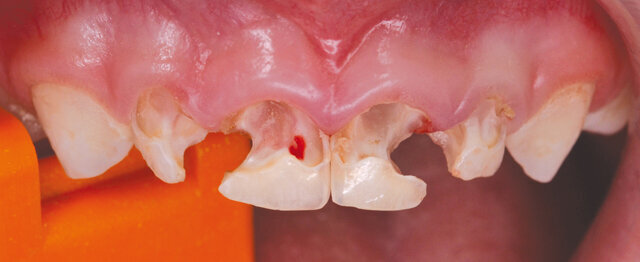

Druhá etapa zahrnovala ošetření horních a dolních řezáků a špičáků. Horní řezáky byly již natolik poškozené (obr. 1), že nebylo možné je rekonstruovat pouze výplněmi, ale bylo třeba ošetřit je korunkami. Proto si dětská zubní lékařka přizvala k tomuto zákroku protetika.

Ošetření bylo zahájeno exkavací kazu horních řezáků, při níž došlo k perforaci do krvácející dřeně zubu 51 a k otevření již po nekróze prázdné dřeňové dutiny zubu 61. Zuby 52, 62 zůstaly vitální (obr. 2). Dětskou zubní lékařkou bylo provedeno endodontické ošetření zubů 51 a 61. Kořenové kanálky byly ručně jemně opracovány, vydesinfikovány 1% chlornanem sodným a zaplněny resorbovatelným materiálem na bázi kalciumhydroxidu s iodofomem (Vitapex). Kořenová výplň byla překryta pod cementosklovinnou hranicí tenkou vrstvou skloionomerního cementu (Fuji IX extra). Zbylé zubní tkáně byly pak protetikem adhezivně připraveny self-etch adhezivem G-aenial (GC), dostavěny do tvaru pahýlů bulkfill kompozitem SDR (Dentsply). Dále byly zuby napreparovány standardní schůdkovou preparací na korunky a opticky naskenovány do CERECu (obr. 3). Poté se dětská zubní lékařka pustila do sanace dolního frontálního úseku fotokompozitními výplněmi a protetik se věnoval výrobě korunek.